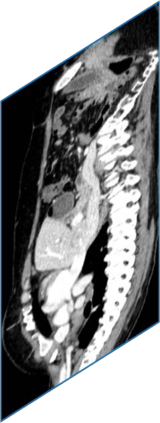

Due to the constraints of the imaging device and high cost in operation time, computer tomography (CT) scans are usually acquired with low intra-slice resolution. Improving the intra-slice resolution is beneficial to the disease diagnosis for both human experts and computer-aided systems. To this end, this paper builds a novel medical slice synthesis to increase the between-slice resolution. Considering that the ground-truth intermediate medical slices are always absent in clinical practice, we introduce the incremental cross-view mutual distillation strategy to accomplish this task in the self-supervised learning manner. Specifically, we model this problem from three different views: slice-wise interpolation from axial view and pixel-wise interpolation from coronal and sagittal views. Under this circumstance, the models learned from different views can distill valuable knowledge to guide the learning processes of each other. We can repeat this process to make the models synthesize intermediate slice data with increasing inter-slice resolution. To demonstrate the effectiveness of the proposed approach, we conduct comprehensive experiments on a large-scale CT dataset. Quantitative and qualitative comparison results show that our method outperforms state-of-the-art algorithms by clear margins.